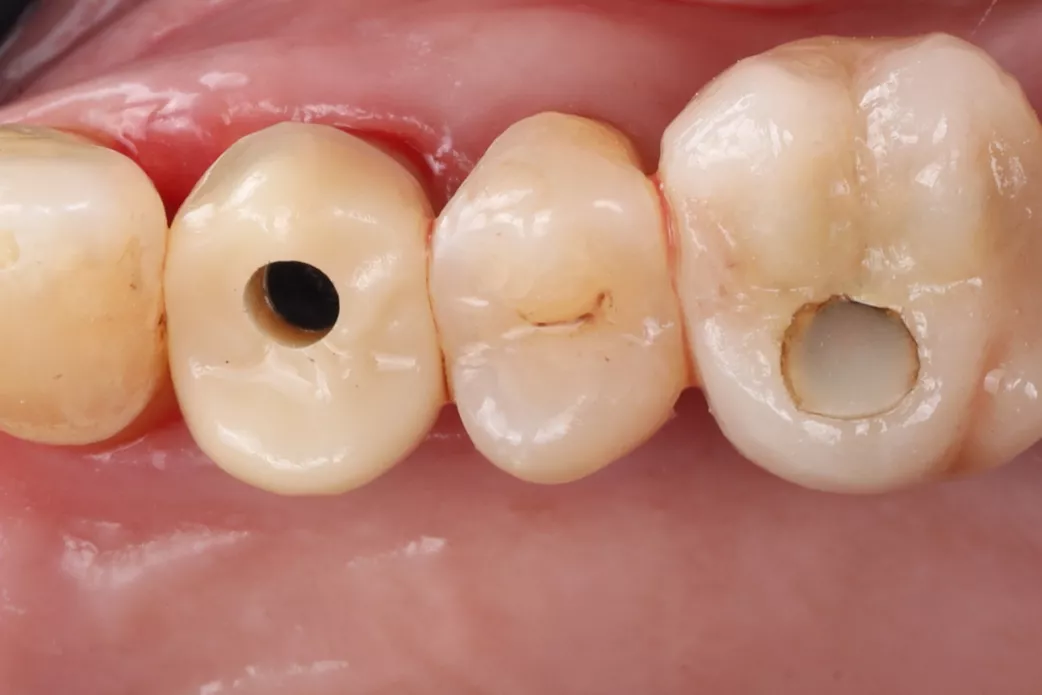

A 78-year-old male in good general health, with no medication and a negative smoking history, presented with mobility of the maxillary right second premolar (tooth 15) (Fig 1a. 1b). Clinical examination revealed severe occlusal wear, plaque accumulation, subgingival calculus, bleeding on probing, and multiple carious lesions. Periodontal assessment showed probing depths >10 mm and grade III mobility. CBCT confirmed circumferential vertical bone loss around tooth 15 and generalized periodontal involvement, indicating a hopeless prognosis and the need for extraction (Fig 1c).

1a. 1b. 1c. CBCT and panoramic views showing severe bone loss around tooth 15, confirming hopeless prognosis.